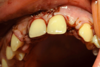

Agénesie bilatérale 52 présente en bouche Traitement ortho conservant l’espace pour 22 chez une jeune fille de 20 ans |

Côté droite

Côté gauche |